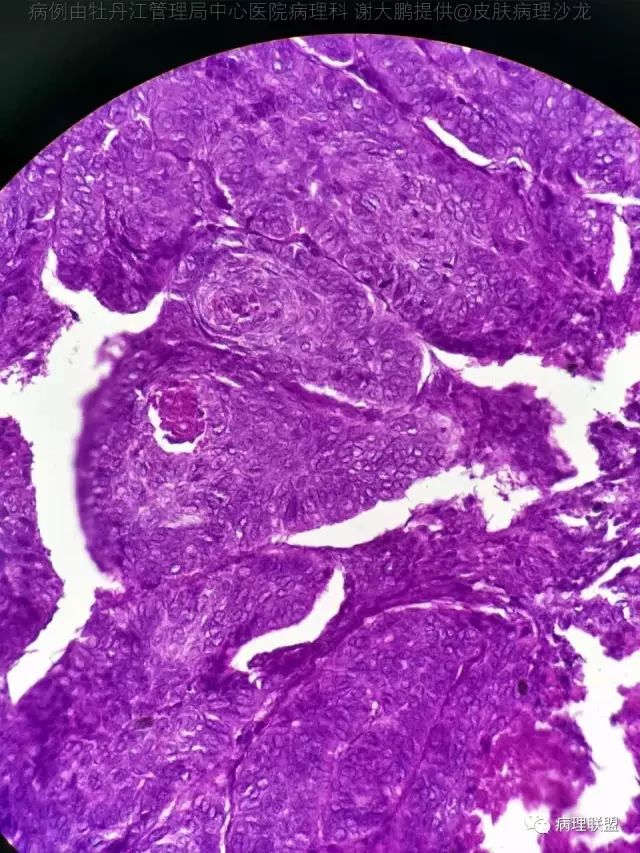

69岁,鼻翼肿物2年,1.5厘米大小,麻烦老师们帮忙看看,谢谢(病例由牡丹江管理局中心医院病理科 谢大鹏提供,致谢!)